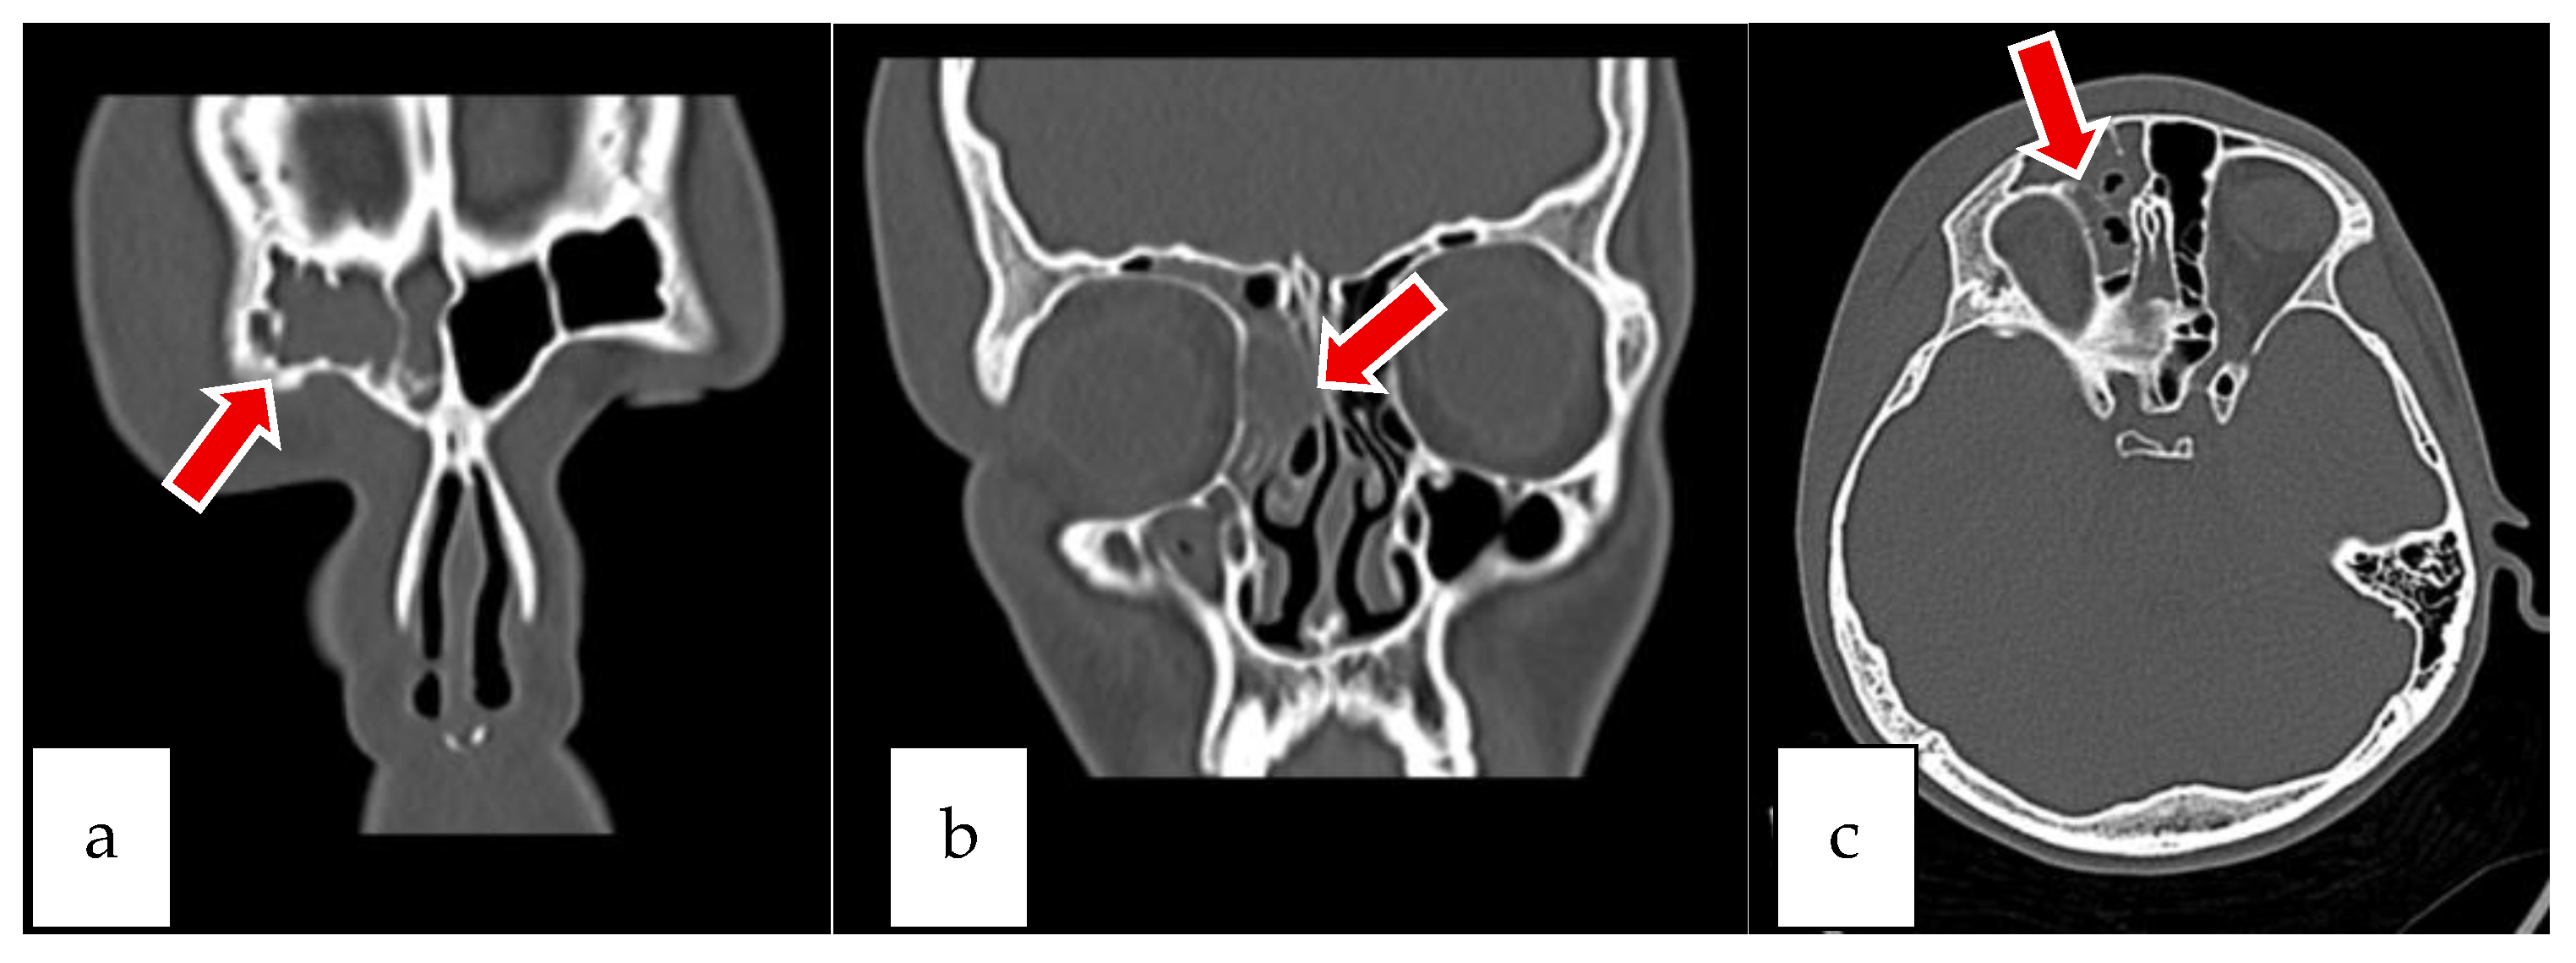

2.1. Case 1

2.2. Case 2